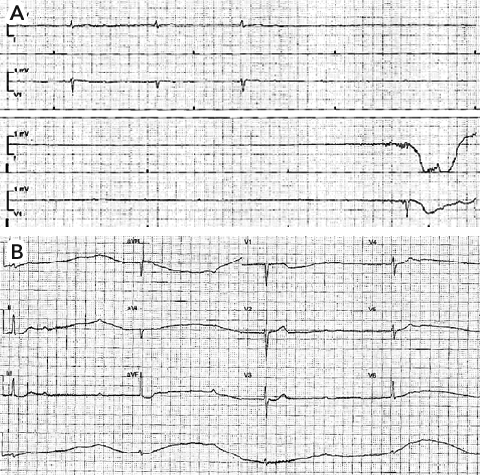

While undergoing cardiac monitoring in the emergency department, the patient experienced a further episode of syncope. Telemetry (Box 1, A) and an electrocardiogram (ECG) (Box 1, B) demonstrated complete heart block. An atropine bolus was administered and an isoprenaline infusion commenced. The initial ECG performed after commencement of isoprenaline demonstrated 2:1 heart block. The patient’s serum electrolyte levels were normal.

1 Patient’s telemetry and electrocardiogram (ECG) traces

Cardiac monitoring telemetry trace (A) and ECG (B) showing complete heart block. |